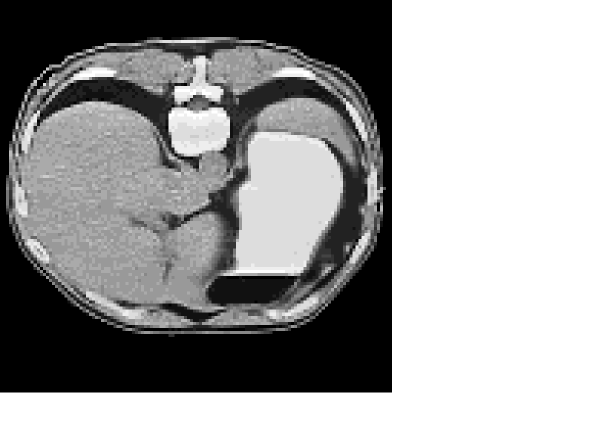

To simulate the internal data |J|𝐽|J|, we use an abdominal human CT image rescaled to a realistic range of tissue conductivity, with values varying from 1 to 1.8 S/m The scaled conductivity distribution, on a uniform grid 128×128128128128\times 128, is shown in Figure 1.

Refer to caption

Figure 1: The original conductivity distribution used in the data simulation.